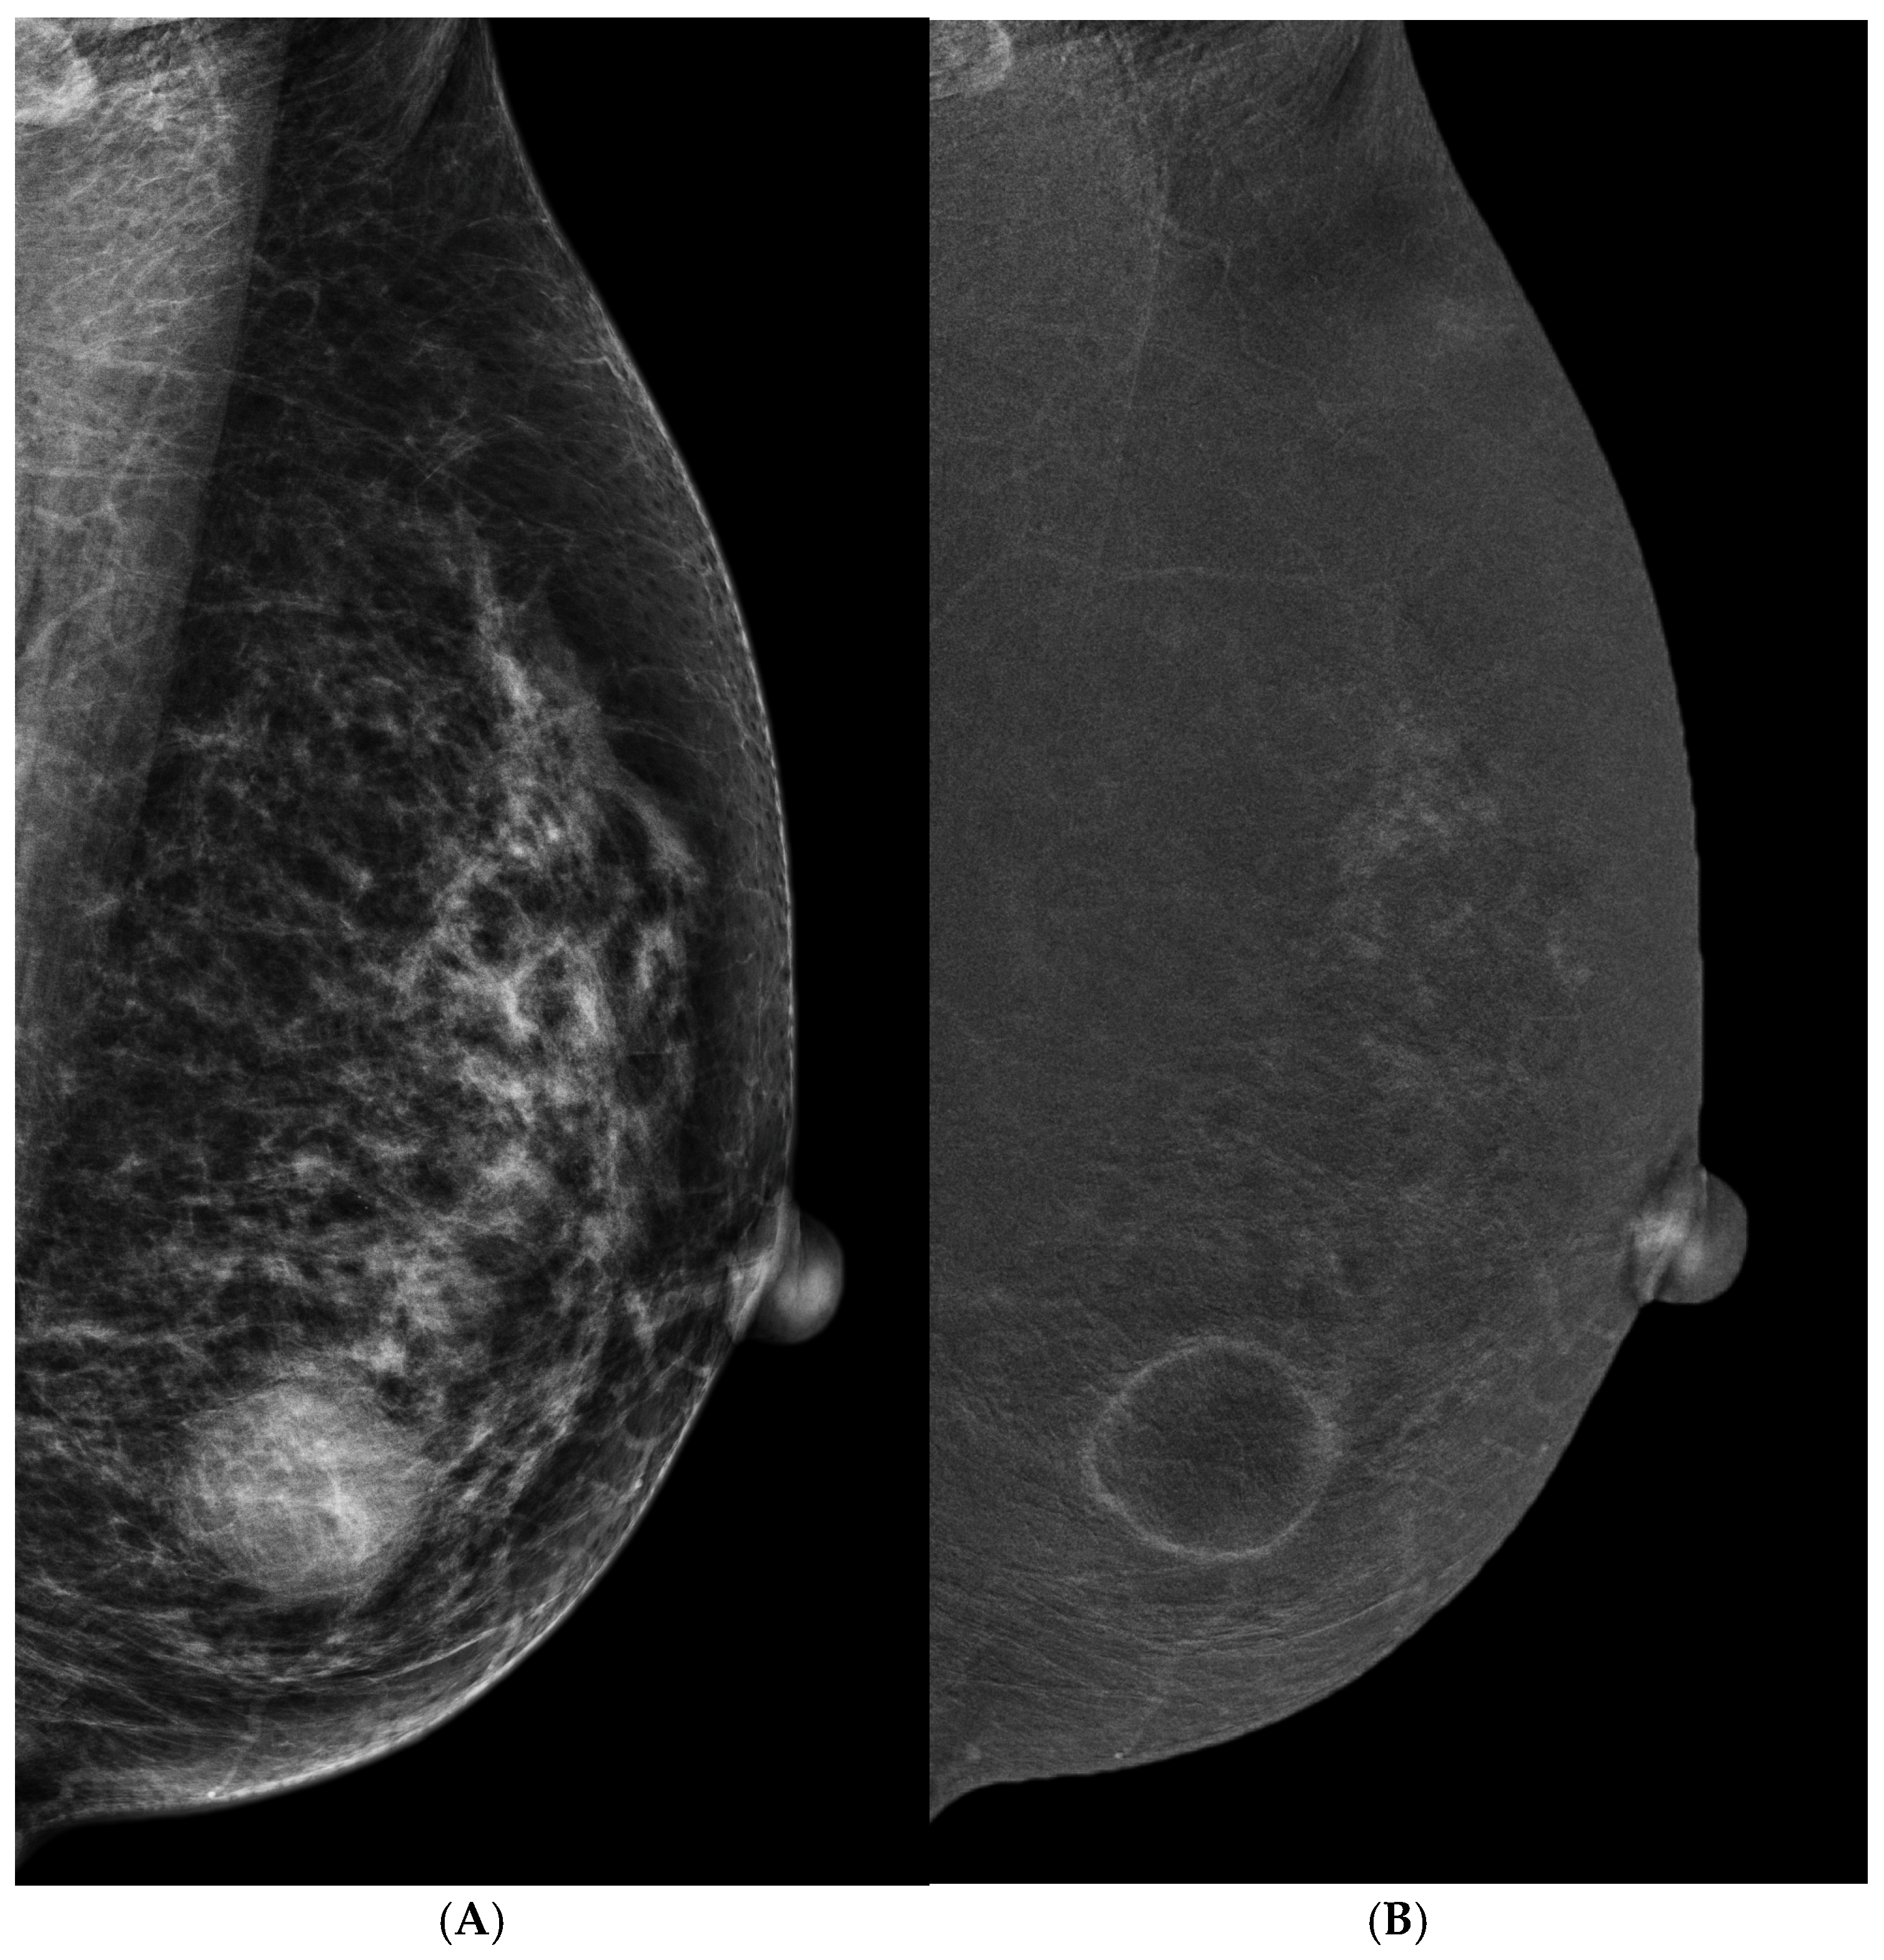

- Cheung, Y.C.; Tsai, H.P.; Lo, Y.F.; Ueng, S.H.; Huang, P.C.; Chen, S.C. Clinical utility of dual-energy contrast-enhanced spectral mammography for breast microcalcifications without associated mass: A preliminary analysis. Eur. Radiol. 2016, 26, 1082–1089. [Google Scholar] [CrossRef] [PubMed]

- Cheung, Y.C.; Juan, Y.H.; Lin, Y.C.; Lo, Y.F.; Tsai, H.P.; Ueng, S.H.; Chen, S.C. Dual-Energy Contrast-Enhanced Spectral Mammography: Enhancement Analysis on BI-RADS 4 Non-Mass Microcalcifications in Screened Women. PLoS ONE 2016, 11, e0162740. [Google Scholar] [CrossRef] [PubMed]

- Houben, I.P.; Vanwetswinkel, S.; Kalia, V.; Thywissen, T.; Nelemans, P.J.; Heuts, E.M.; Smidt, M.L.; Meyer-Baese, A.; Wildberger, J.E.; Lobbes, M. Contrast-enhanced spectral mammography in the evaluation of breast suspicious calcifications: Diagnostic accuracy and impact on surgical management. Acta Radiol. 2019, 60, 1110–1117. [Google Scholar] [CrossRef] [PubMed]

- Long, R.; Cao, K.; Cao, M.; Li, X.T.; Gao, F.; Zhang, F.D.; Yu, Y.Z.; Sun, Y.S. Improving the Diagnostic Accuracy of Breast BI-RADS 4 Microcalcification-Only Lesions Using Contrast-Enhanced Mammography. Clin. Breast Cancer 2021, 21, 256–262.e2. [Google Scholar] [CrossRef]

- Nicosia, L.; Bozzini, A.C.; Signorelli, G.; Palma, S.; Pesapane, F.; Frassoni, S.; Bagnardi, V.; Pizzamiglio, M.; Farina, M.; Trentin, C.; et al. Contrast-Enhanced Spectral Mammography in the Evaluation of Breast Microcalcifications: Controversies and Diagnostic Management. Healthcare 2023, 11, 511. [Google Scholar] [CrossRef]

- Depretto, C.; D’Ascoli, E.; Della Pepa, G.; Irmici, G.; De Berardinis, C.; Ballerini, D.; Bonanomi, A.; Ancona, E.; Ferranti, C.; Scaperrotta, G.P. Assessing the malignancy of suspicious breast microcalcifications: The role of contrast enhanced mammography. La Radiol. Medica 2024, 129, 855–863. [Google Scholar] [CrossRef]